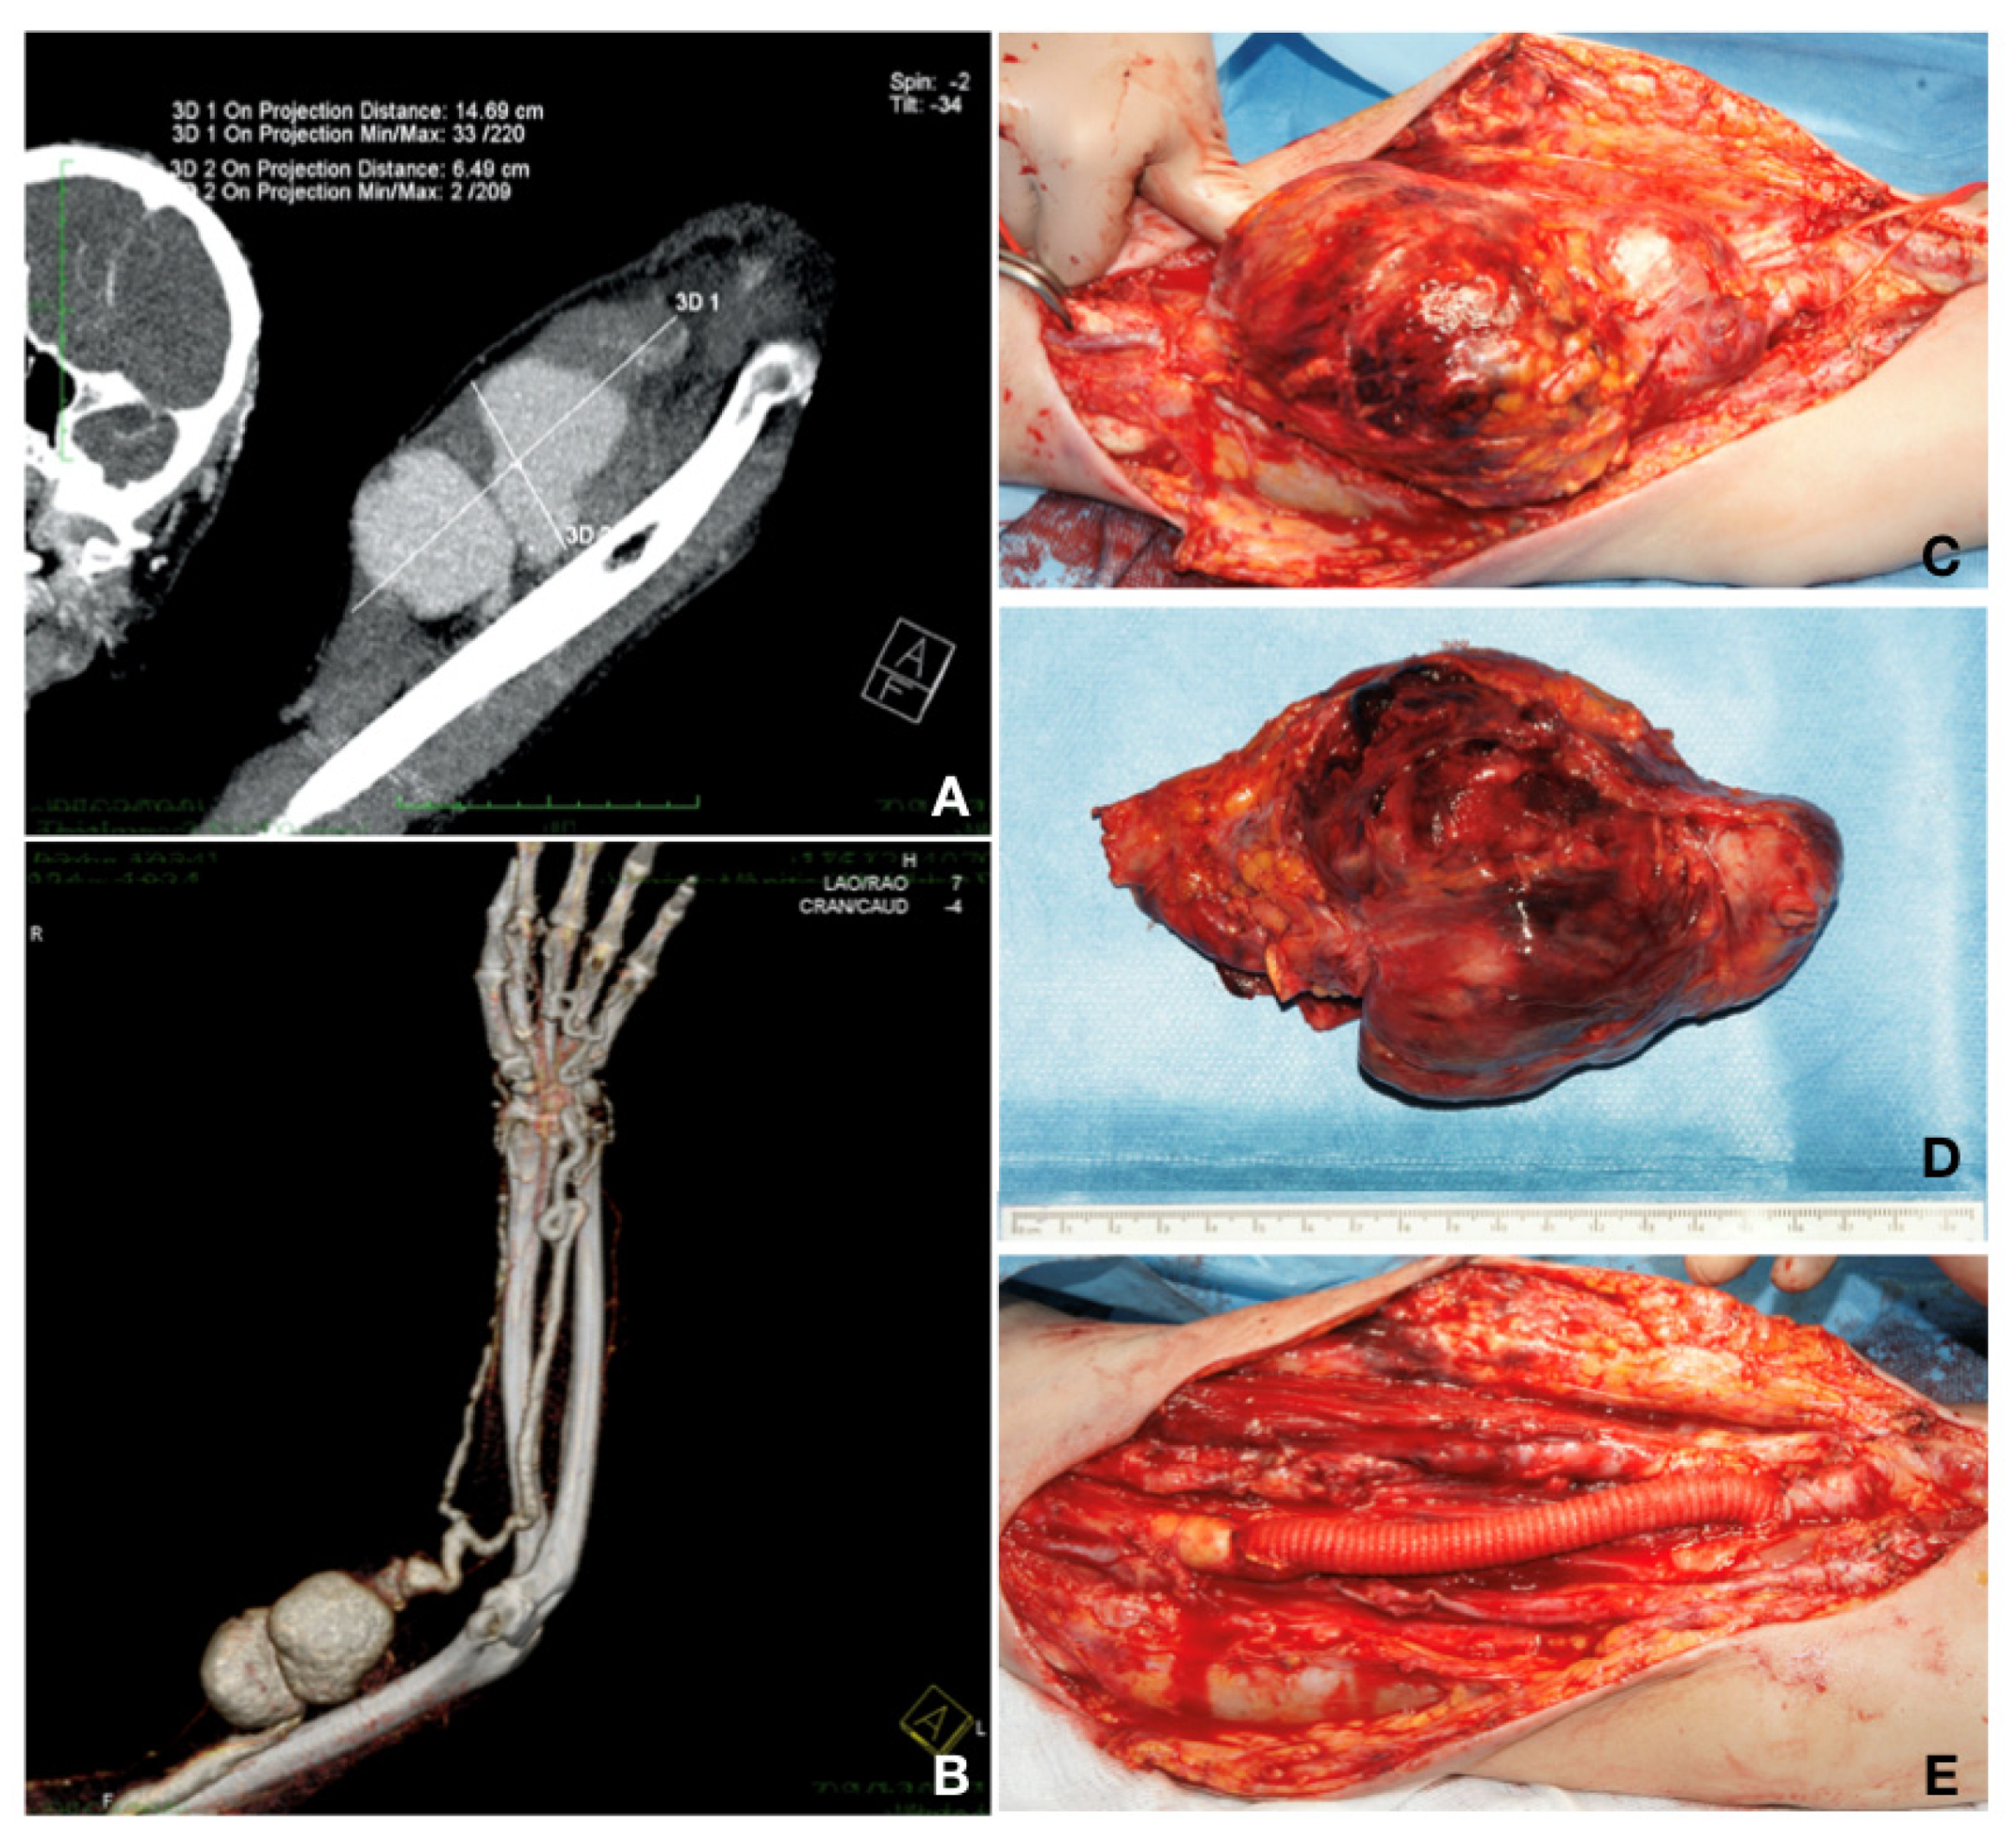

Case 2. A 42-year-old patient presented with a pulsatile mass in the upper left arm, with a skin erosion and the loss of the grip strength, also known to have chronic renal disease stage 5 KDIGO and Alport syndrome, and having undergone a live-donor RT 8 years prior. The patient had palpable radial and ulnar pulses. He had, on the same arm, a radio-cephalic AVF, closed 6 years before with radial artery reconstruction and cephalic vein thrombosis. He was on immunosuppressive and steroid agents (mycophenolic acid 2 × 180 mg and prednisone 5 mg daily). He underwent a CT-Angio investigation that showed a brachial artery aneurysm of 14.69/6.49 cm. The patient did not require hemodialysis after the investigation because the level of creatinine was constant at 4 mg/dL at 48 and 72 h after the investigation, respectively. Furthermore, for this patient, aneurysm resection and vascular reconstruction were performed. The patient received preoperatively an adjusted dose of Vancomycin

® (Fresenius Kabi, Brasov, Romania) at 1 g/dosage for infection prevention. Aneurysm resection and reconstruction with a collagen-impregnated woven nylon graft (Dacron

®; Vascutek, Terumo) of 10 mm in diameter and end-to-end anastomosis with 6.0 Prolene

® (BBraun, Hessen, Germany) continuous sutures were performed under general anesthesia. This vascular graft was chosen due to the arterial diameter (more than 10 mm), arterial wall thickness (approximately 2 mm and anfractuous structure), and because the saphenous vein of the patient was not fit for the procedure (1.5 mm in diameter, as previously measured by ultrasound). The postoperative evolution was without complications on the surgical site (embolic, neurological, bleeding, or infection at the surgical site). A week after the vascular reconstruction, the patient developed constrictive pericarditis and needed a pericardial window. Two months after surgery, the patient developed a chronic rejection of the transplanted kidney and required nephrectomy. The status of the patient deteriorated rapidly, and he died 3 months after reconstruction (

Figure 3).